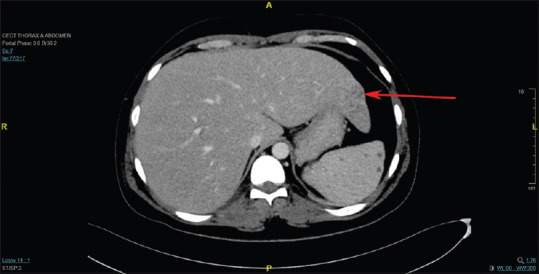

Melioidosis is a disease endemic to India but often goes unrecognized, leading to considerable illness and death. We present the case of a 31-year-old man who had a fever of unknown origin, abnormal renal and liver function tests, and negative tests for dengue, typhoid, leptospirosis, and scrub typhus. Imaging revealed multiple splenic infarcts. Initially suspected to be malaria due to its prevalence in South India, further investigation uncovered pneumonia along with several liver and splenic abscesses, raising the possibility of melioidosis. Blood culture eventually identified Burkholderia pseudomallei, confirming the diagnosis. As malaria cases decline in Southeast Asia, emergency physicians should consider melioidosis in their differential diagnosis of acute febrile illnesses, especially in endemic areas. Early detection and prompt antibiotic treatment are vital for managing this often under-recognized disease with a high fatality rate. Thus, melioidosis should be considered in patients with unexplained fever in endemic regions, as early diagnosis and intervention can be life-saving.